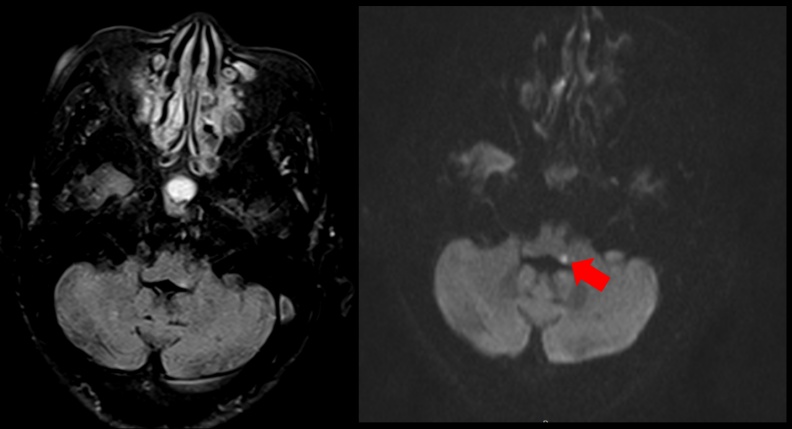

恩主公醫院神經內科朱海瑞醫師日前收治一名80歲的老婦,本身有糖尿病與高血壓,在某天起床時感到頭暈目眩,甚至想吐,家人以為是剛起床還沒吃飯血糖過低,但是後來吃完早餐後,仍覺得頭暈不適,被家人送至急診就醫,因考量到婦人80歲的高齡還有心血管病史,因此會診神經內科,透過腦部核磁共振檢查,診斷老婦人是腦幹梗塞型中風。

朱海瑞表示,暈眩原因可分為「周邊型眩暈」以及「中樞型眩暈」,前者和耳部的前庭系統受影響有關,分為前庭神經炎、梅尼爾氏症,良性陣發性姿勢性眩暈等,這類型感到的是天旋地轉的暈,而中樞型眩暈最常見於小腦及腦幹中風患者,可能伴隨著腦中風典型狀況。